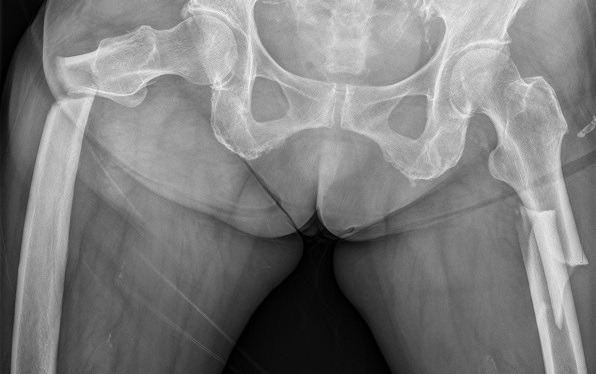

(* 사진설명: 77세 여성으로 골다공증 주사 2년 후 골밀도 수치가 아주 높게 나와 약의 효과에 만족함)

(* 사진설명: 마지막 내원 얼마 후 길에서 넘어져 발생한 양측 대퇴골 골절로 응급실에 실려 옴)

위 사례처럼 사소한 충격에 심각한 골절이 일어난 것이 비전형 골절인데, 정상인에서는 생길 수 없는 골절 양상으로 포사맥스 출시 10년 후인 2005년에 보고서가 처음 나왔다. (*정상인에서 저 정도의 골절이 생기려면 덤프트럭에 받힌 정도의 충격을 받았을 경우일 것이다.)

보고서에 따르면 포사맥스를 평균 5.4년 복용한 후 사소한 충격에 골절이 발생한 9명의 환자를 분석해보니, 골대사를 심하게 억제하는 골다공증약을 장기간 사용시, 일상에서 정상적으로 발생할 수 있는 미세손상(microcrack)의 회복이 더디고, 뼈의 무기질화가 과하게 되어(hypermineralization) 골밀도는 증가하나 뼈가 딱딱해져 오히려 더 쉽게 부러질 수 있고(brittle), 골재형성(bone remodeling) 능력이 저하되어 부러진 뼈가 잘 붙지도 않는다고 하였다 [37]. 즉 뼈를 튼튼하게 하기 위해 먹은 약들이 아이러니하게도, 뼈를 더 약하게 만들고 있었다 [38].